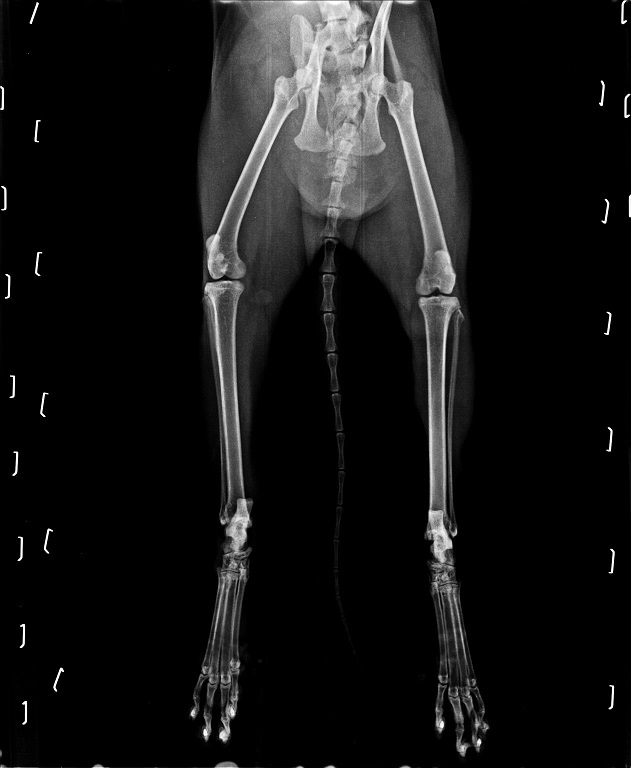

同同到了醫院後先鎮靜拍了X光照片檢查,

發現骨盆及兩條後腿都已經骨折,

且骨頭易位壓迫神經,

導致同同的後腿已經沒有知覺也沒辦法使力....